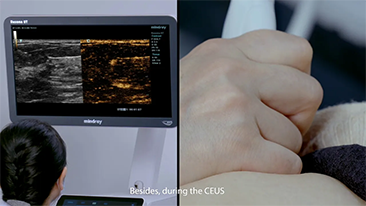

Hoe duidelijk is een lever te zien?

Bij focale leverlaesies, zoals hemangioom of leverkanker, speelt ultrasone contrastbeeldvorming een belangrijke rol. Ultrabrede niet-lineaire UWN+ contrastbeeldvormingstechnologie kan helpen bij het verkrijgen van een betere penetratie, een hogere contrast-weefselverhouding, met een lagere MI en een langere observatie van de perfusietijd.